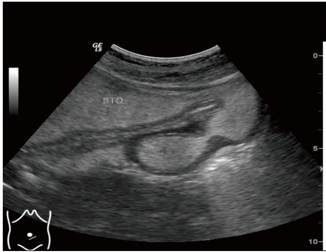

消化性溃疡主要指发生在胃和十二指肠球部的慢性溃疡,其形成与胃酸/胃蛋白酶的消化有关。发病的原因主要是幽门螺杆菌感染引起的炎症和胃酸分泌的异常以及非甾体类药物(NSAIDs)等。临床症状: 上腹痛(部分可与进食相关) 腹胀、嗳气 …